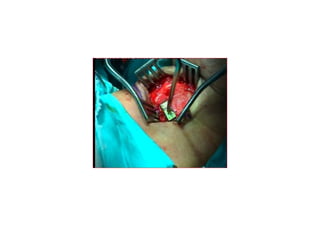

MedializasyonMedializasyon (Tip I)(Tip I) tiroplastitiroplasti

TTiroidiroid kk kk rdakta ardakta açç lanlan penceredenpencereden

yerleyerle((tirilen birtirilen bir implantimplant aracarac ll ileile

VFVF’’ unun medialmedialee itilmesiitilmesi

5 mm

PreopPreop

PostopPostop

1. hafta1. hafta

3. ay3. ay

MedializasyonMedializasyon (Tip I)(TipI) tiroplastitiroplasti TTiroidiroid kk kk rdakta ardakta açç lanlan penceredenpencereden yerleyerle((tirilen birtirilen bir implantimplant aracarac ll ileile VFVF’’ unun medialmedialee itilmesiitilmesi